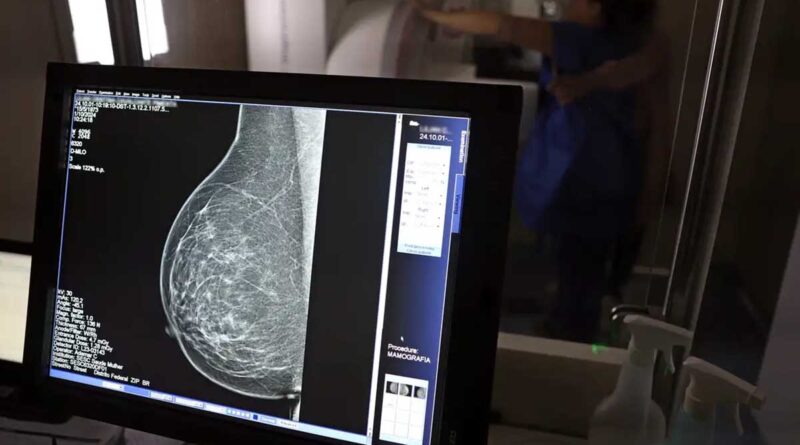

Ministério da Saúde passa a recomendar mamografia a partir dos 40 anos

Faixa de 40 a 49 anos concentra 23% dos casos de câncer de mama

O Ministério da Saúde passou a recomendar o acesso a mamografia, via Sistema Único de Saúde (SUS), para mulheres de 40 a 49 anos – mesmo que não haja sinais ou sintomas de câncer de mama. De acordo com a pasta, a faixa etária concentra 23% dos casos da doença, e a detecção precoce aumenta as chances de cura.

Até então, a orientação era que o exame fosse feito a partir dos 50 anos.

A medida faz parte de um conjunto de ações anunciadas nesta terça-feira (23) voltado para a melhoria do diagnóstico e da assistência. A recomendação para mulheres a partir dos 40 anos é que o exame seja feito sob demanda, em decisão conjunta com o profissional de saúde.

“A paciente deve ser orientada sobre os benefícios e desvantagens de fazer o rastreamento. Mulheres nesta idade tinham dificuldade com o exame na rede pública de saúde por conta da avaliação de histórico familiar ou necessidade de já apresentar sintomas”, informou o ministério em nota.

As mamografias via SUS em pacientes com menos de 50 anos, de acordo com a pasta, representam 30% do total, o equivalente a mais de 1 milhão apenas no ano de 2024.

Outra medida anunciada é a ampliação da faixa etária para o rastreamento ativo – quando a mamografia é solicitada de forma preventiva a cada dois anos. A idade limite, até então, era 69 anos. Agora, passa a ser 74 anos. Dados do ministério revelam que quase 60% dos casos de câncer de mama estão concentrados entre 50 e 74 anos.

“A ampliação do acesso à mamografia aproxima o Brasil de práticas internacionais, como as adotadas na Austrália, e reforça o compromisso em garantir diagnóstico precoce e cuidado integral às mulheres brasileiras. O câncer de mama é o mais comum e o que mais mata mulheres, com 37 mil casos por ano”, reforçou a pasta.

Os números mostram que, em 2024, cerca de 4 milhões de mamografias para rastreamento e 376,7 mil exames diagnósticos foram realizados no SUS.